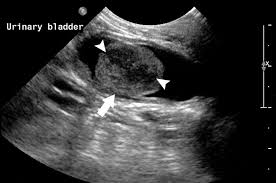

Bladder Tumor Animal Cancer And Imaging Center from images.squarespace-cdn.com The cause is often stress, which causes inflammation of the nerves in the bladder wall. Symptoms of urinary bladder cancer in cats the first signs of urinary bladder cancer mimic those of a bladder infection and most pet owners interpret straining to urinate, frequent urination, and urinary incontinence as a simple bacterial infection. The urine may look darker than usual, brownish, or. Cancer in cats can be very difficult to find, as cats can easily hide their pain. Some incontinent cats can have larger bladders because over time the bladder walls have stretched to accommodate the retained urine. The lymph nodes behind the knees and under the jaws are easiest to find. Blood in urine blood in the urine can be a sign of bladder cancer, either visible to the eye or picked up by routine testing. It is important to differentiate bladder cancer from a urinary tract infection and urinary tract stones, which may cause similar symptoms.

If your cat's uretha becomes blocked and he can't urinate, he could die from a condition called uremia, in fewer than three days. Bladder cancer symptoms cat bladder cancer symptoms include difficulty urinating, frequent need to urinate while passing only small amounts of urine, blood in the urine, straining to defecate, and difficultly breathing. The cause is often stress, which causes inflammation of the nerves in the bladder wall. Some of cat cancer symptoms that you should have an eye on them : Symptoms of bladder cancer are very similar to other disorders of the urinary tract such as cystitis, urinary crystals/stones and urinary tract infection.

Some cats might express an inability to urinate as well. And because cats have a tendency to mask illnesses, it. This is inflammation of the bladder wall which leads to cat uti signs. 12 warning signs of cancer in cats. Bladder stones irritate the lining of the bladder blood in the urine, straining to urinate and increased frequency of urination. Symptoms of urinary bladder cancer in cats the first signs of urinary bladder cancer mimic those of a bladder infection and most pet owners interpret straining to urinate, frequent urination, and urinary incontinence as a simple bacterial infection. Loss of appetite and weight loss. In cats, it can develop anywhere in the bladder or urethra. For a healthy continent cat, a full bladder is somewhere between the size of a handball and a golf ball, while the bladder of an incontinent cat can sometimes be as large as a large grapefruit. Bladder cancer symptoms cat bladder cancer symptoms include difficulty urinating, frequent need to urinate while passing only small amounts of urine, blood in the urine, straining to defecate, and difficultly breathing. Bladder cancer symptoms the bladder cancer symptoms can be manifested in the very early stages depending on the location of the tumor. Rhabdomyosarcoma of the urinary bladder may be reported as botryoid rhabdomyosarcomas due to their tendency to take on the appearance of grape clusters. Symptoms of bladder cancer are very similar to other disorders of the urinary tract such as cystitis, urinary crystals/stones and urinary tract infection.